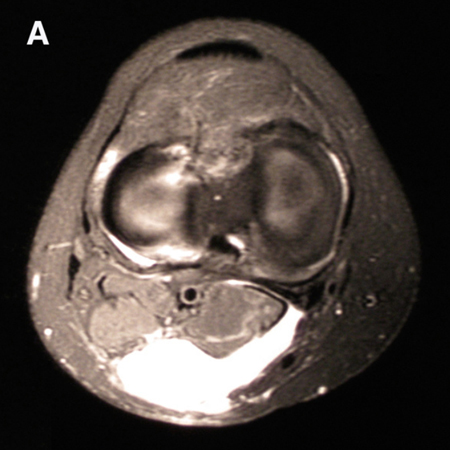

MRI depicting cyst in interval of medial gastrocnemius and semimembranosus

From the collection of Dr John D. Kelly IV; used with permission